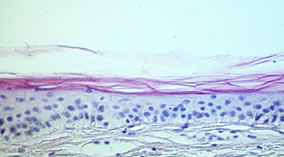

Gealterte Haut ist auf den ersten Blick durch das Auftreten von Falten, Schlaffheit und Altersflecken zu erkennen. Im histologischen Schnitt erkennt man auch einige Ursachen für diese Alterszeichen (Abb. 1).

Abb. 1: Mikroskopische Schnitte durch die Haut von einer 29-Jährigen (oben) und einer 69-Jährigen (unten)

In junger Haut ist der untere Teil der Haut, die Dermis sehr regelmäßig aufgebaut. Diese klare Struktur ist im Alter gestört: Die Dermis enthält unregelmäßige Strukturen und Auflockerungen und erscheint weniger kompakt. Die nächsthöhere Schicht, die Epidermis, ist im Alter etwas dünner als in junger Haut. Viel auffälliger als diese geringe Änderung der Epidermisdicke ist aber das Verschwinden der Krümmungen der epidermalen-dermalen Grenzfläche. In gealterter Haut ist diese Grenzfläche flach, was zu einer Schwächung der Kohäsion zwischen Dermis und Epidermis führt. In der obersten Schicht schließlich, dem Stratum Corneum, sind im Mikroskop kaum Unterschiede festzustellen.